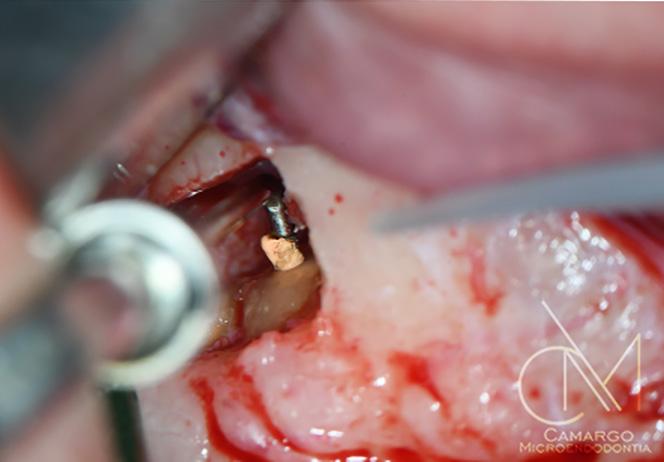

Enfoque regenerativo usando microcirugía endodóntica

Salvar los dientes afectados por defectos periapicales de grandes dimensiones

Cuando se trata de salvar los dientes, el éxito clínico depende en gran medida de los tratamientos periodontales y endo dónticos.1 De hecho, los dientes que se pierden durante el tratamiento perio dontal y los llamados «dientes insalva bles» suelen presentar problemas endo dónticos.

En los tratamientos endodónticos no quirúrgicos, los dentistas eliminan cui dadosamente la caries, la pulpa infla mada o infectada, limpian, desinfectan y conforman los conductos radiculares, y colocan una obturación para sellar el conducto. La tasa de éxito de este tra tamiento es menor cuando las lesiones

periapicales son extensas. En estos ca sos, el tratamiento endodóntico quirúr gico es una alternativa.

Las lesiones periapicales se encuentran entre las lesiones patológicas más comu nes en el hueso alveolar.2 Este tipo de le siones provoca defectos óseos y, cuando son grandes, el organismo no es capaz de regenerar hueso nuevo para rellenar los. Entonces el tejido conectivo invade el defecto óseo y afecta a los resultados clínicos.3

Injertar el defecto con un sustituto óseo y cubrirlo con una membrana reabsorbi ble puede ayudar al organismo a corregir

el defecto. En los tratamientos endodón ticos regenerativos para defectos gran des, como con la terapia periodontal regenerativa, los dentistas usan hueso autógeno y biomateriales, o una mezcla de ambos.

Los endodoncistas deberían diagnosti car la situación clínica, incluido el acceso al conducto, la ubicación y la anatomía de los dientes y de los tejidos circundan tes, y en caso de recidiva, la calidad del tratamiento endodóntico más reciente. Solo así es posible hacer un tratamien to no quirúrgico o quirúrgico apropiado.

Microcirugía periapical regene rativa

La microcirugía periapical regenerativa emplea los principios fundamentales de la endodoncia, la periodoncia y la odonto logía oral y restauradora. Por lo general, el objetivo del tratamiento es eliminar todos los posibles factores causantes de lesio nes periapicales, reparar la arquitectura del tejido periapical perdido y conservar la estructura y la anatomía de la raíz y de los tejidos blandos. También es importan te prevenir la recidiva de la enfermedad a largo plazo.

En lugar de extraer o sustituir los dientes con implantes dentales, los endodoncistas prefieren prolongar la funcio‑ nalidad de las piezas dentales con raíces con traumatismo. Los avances actuales en la tecnología, los procedimientos y los biomateriales, permiten a estos especialistas salvar los dientes con una increíble tasa de éxito.

| A Tomografía computarizada de haz cónico (CBCT) coronal o sagital que muestra la proximidad de la lesión periapical y el seno maxilar. | B Oclusión correcta antes del tratamiento. | C Plantilla quirúrgica 3D para guiar el acceso. | D Osteotomía con el Piezotome Cube (Acteon, EE. UU.) usando la punta SL1 después de elevar el colgajo. | D Osteotomía con el Piezotome Cube (Acteon, EE. UU.) usando la punta SL2 | F Preparación retrógrada sobre la raíz mesiovestibular con una punta Berutti (EMS, Suiza) e irrigación salina. | G Biocemento Bio C Repair (Angelus, Brasil) aplicado en el conducto mesiovestibular. | H Fotografía con el microespejo de 3 mm para comprobar la obturación retrógrada en la raíz distovestibular del segundo molar derecho superior. | I Geistlich Bio-Oss® Small 0,5 g. (Geistlich Pharma AG, Suiza) en el sitio quirúrgico. | J Cavidad quirúrgica rellenada con Geistlich Bio-Oss® Small. | K Membrana Geistlich Bio-Gide® 25 × 25 mm usada para cubrir el injerto. | L Radiografía final después de la cirugía.

17 A B C D E F J K L H I G

FIG. 1: Microcirugía periapical regenerativa para tratar la periodontitis apical alrededor de las raíces mesiovestibular y distovestibular del diente

La microcirugía periapical regenerativa incluye los siguientes pasos (figura 1):

1. Aumento mejorado para una resección mínima de la raíz;

2. Preparación ultrasónica del ápice de la raíz;

3. Obturación retrógrada con un mate rial biocerámico para la reparación de la raíz; y

4. Regeneración tisular guiada en el lu gar del defecto óseo.

Los índices del éxito de la microcirugía periapical regenerativa han aumentado de manera notable en los últimos años gracias a los avances en las técnicas di gitales para la planificación, la microsco pía, los instrumentos microquirúrgicos y los biomateriales para la regeneración ti sular guiada.3 4

La selección de los materiales regenerativos

A pesar de que los injertos autógenos sue len considerarse como el método de re ferencia para la odontología regenerativa, no siempre son la mejor opción. Suelen estar asociados a un dolor y una morbili dad mayores, porque es necesario extraer el injerto. En una revisión sistemática, Chavda y Levin (2018) constataron que los pacientes preferían sustitutos óseos no autógenos, porque se reducían los días de la hospitalización, el dolor era menor y el tiempo de recuperación era más cor to.5 Los autores no observaron ninguna

diferencia en el índice de éxito de los im plantes cuando la cresta alveolar se au mentaba con diferentes injertos óseos, in cluido el hueso autógeno.5

Uso biomateriales para las microcirugías periapicales y, hasta la fecha, estoy muy satisfecho con los resultados clínicos. El protocolo me ha permitido ayudar a mu chos pacientes a conservar sus dientes naturales insalvables, y a mantenerlos sanos y funcionales. Recientemente, mis colegas y yo publicamos un caso clínico donde detallábamos el protocolo y el re sultado clínico en el manejo de una lesión radicular grande mediante microcirugía periapical regenerativa.3 El quiste medía 40 mm en la zona más grande, y afectaba a varios dientes anteriores, a ambas placas corticales y en parte al suelo nasal. Debi do a las grandes dimensiones del defecto, decidimos usar una mezcla de Geistlich Bio‑Oss® y hueso autógeno obtenido de la rama ascendente de la mandíbula, junto con fibrina rica en plaquetas. El resulta do clínico era satisfactorio 4 años después de la cirugía (es decir, en el momento de la publicación). Además, cuando estudia mos las imágenes de la tomografía com putarizada de haz cónico, observamos que los tejidos estaban bien integrados, había hueso cortical nuevo y una radio pacidad y una forma trabecular parecidas a las del hueso nativo adyacente.

Hasta la fecha hay varios estudios que se centran en el uso de biomateriales en la cirugía periapical. Por tanto, cuando bus camos evidencia científica para explicar la regeneración ósea en el interior de las lesiones periapicales, confiamos princi palmente en estudios realizados en otras áreas de la terapia regenerativa. Dada la importancia de usar biomateriales con unos beneficios a largo plazo documenta dos y que tengan un alto nivel de eviden cia en comparación con otros materiales de injerto, los biomateriales de Geistlich son el producto de referencia.7 10